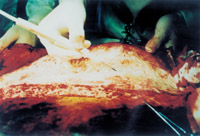

µÚÒ»²½£º¶ÔÉÕÉËÆ¤·ôµÄ´¦Öóͷ£

3-1 ´¦Öóͷ£Ç°ÇéÐÎ

3-4 ÓõçÊÖÊõµ¶´ÓÉÐδ±»ÉÕÉËµÄÆ¤ÏÂ×é֯ϲ㡢Éî½îĤÉϽ«ÉÕÉËÆ¤·ô¼°Æ¤ÏÂ×éÖ¯Ò»ÆðÇгý

3-5 ÕâÊÇÆ¤·ô¼°Æ¤ÏÂ×éÖ¯±»ÇгýºóµÄ´´ÃæÇéÐΣ¬£¬£¬ £¬ £¬£¬£¬£¬ÌåÏÖΪÉî½îĤ±£´æµÄ¼¡Èâ²ã´´Ãæ

3-6 ´¦Öóͷ£Ð§¹û£ºÉÕÉËÆ¤·ô¼°Î´ÉÕÉËµÄÆ¤ÏÂ×éÖ¯¾ù±»Çгý£¬£¬£¬ £¬ £¬£¬£¬£¬Ðز¿ÉÕÉË´´ÃæÄð³ÉÈËΪµÄÍâ¿ÆÊÖÊõÇгýµÄ¼¡Èâ²ã´´ÉË´´Ã棬£¬£¬ £¬ £¬£¬£¬£¬ÒÑÎÞÈκÎÉÕÉË×éÖ¯¼°Æ¤·ô×éÖ¯¡£¡£¡£¡£¡£¡£¡£